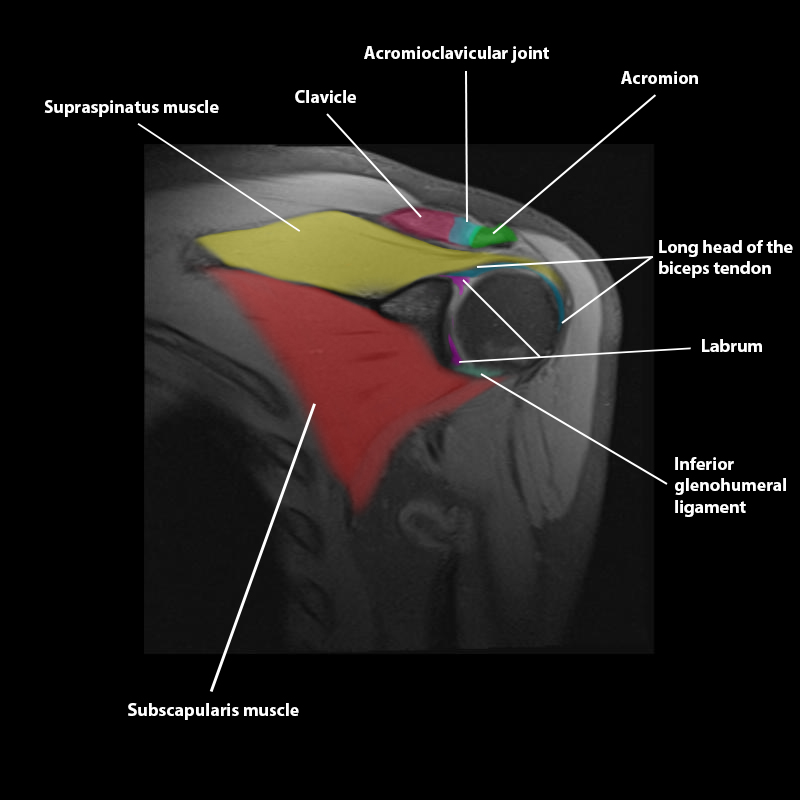

Shoulder MRI Anatomy